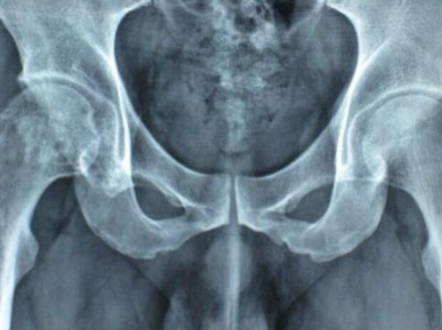

郑州股骨头医院:股骨头坏死都有什么症状?

郑州股骨头医院介绍股骨头坏死是骨科比较常见的一种疾病,有被称之为不死的癌症之说,可见…[详情]